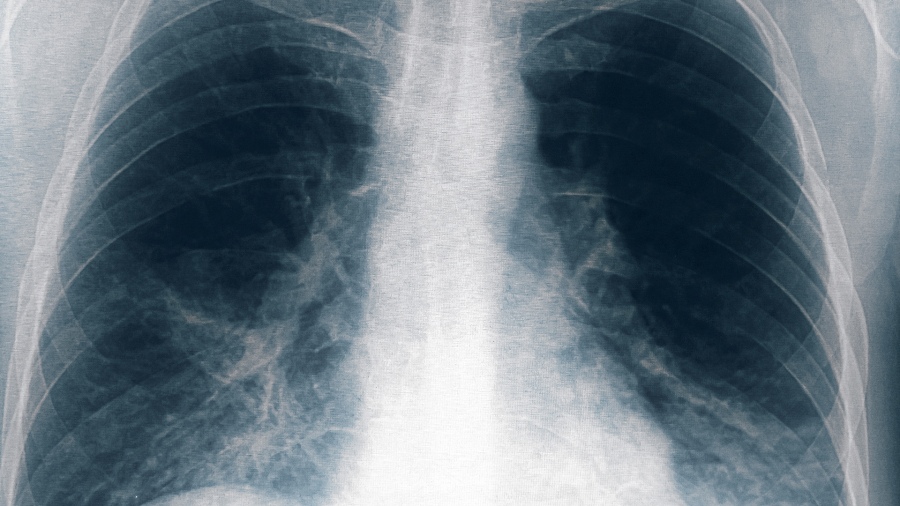

Otras ocho personas resultaron afectadas por el brote de neumonía bilateral causado por la bacteria legionella, una de ellas en estado grave, tras un cambio en el criterio de selección de los pacientes, con lo que suman 13 casos en total y seis fallecidos, informó el ministro de Salud de Tucumán, Luis Medina Ruiz.

«En general, esta enfermedad produce una mortalidad del 10 o 20% y es mucho mayor cuando se trata de neumonías», indicó el médico y añadió que «la mayoría de las personas que están graves o fallecieron son mayores, con comorbilidades severas.»